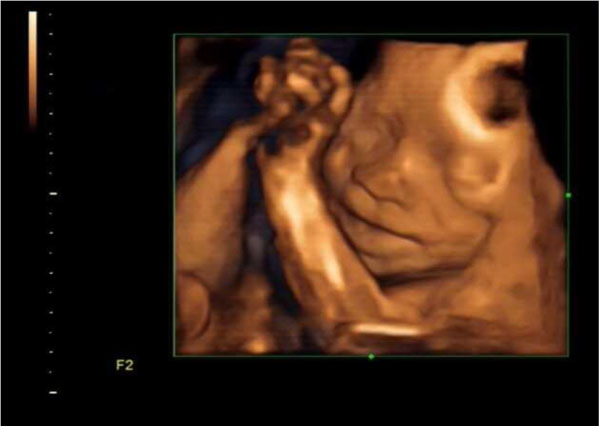

Fig. (4I). 4D Ultrasound Imaging of Fetal Face at the beginning of the test for a Group A Patient.

Fig. (4II). Successful 4D Ultrasound Imaging of Fetal Face with clear facial features post 5 minutes of Knee-Chest Decubitus Position for that same Group A Patient.